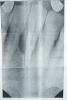

bolnoi_zub Опубликовано 23 марта, 2011 Поделиться Опубликовано 23 марта, 2011 Неделю мучаюсь с больной десной у нижних передних зубов. Ходил к стоматологу, сделали снимок Сама десна воспалилась этаким бугорком. Если сильно нажать, то идет кровь, немного, но идет. Бугорок плотный, не гнойный. Хотя я не дохтор. Врач сказал полоскать солью+сода+йод. Полоскал, было улучшение, но не надолго. Боль стихает, но бугорок на месте, правда меньшего размера. Зуб подвижен, шатается. Как и чем такое лечить? Доктор сказал, что если не поможет, то надо вскрывать и чистить (типа там отмершие нервы, остатки костной ткани), а потом подвижный зуб скреплять с соседними, чтобы окончательно не выпал. Такое у меня было лет 5 назад, ходил на прогревание и пил жидкий кальций, плюс полоскал. Ссылка на комментарий